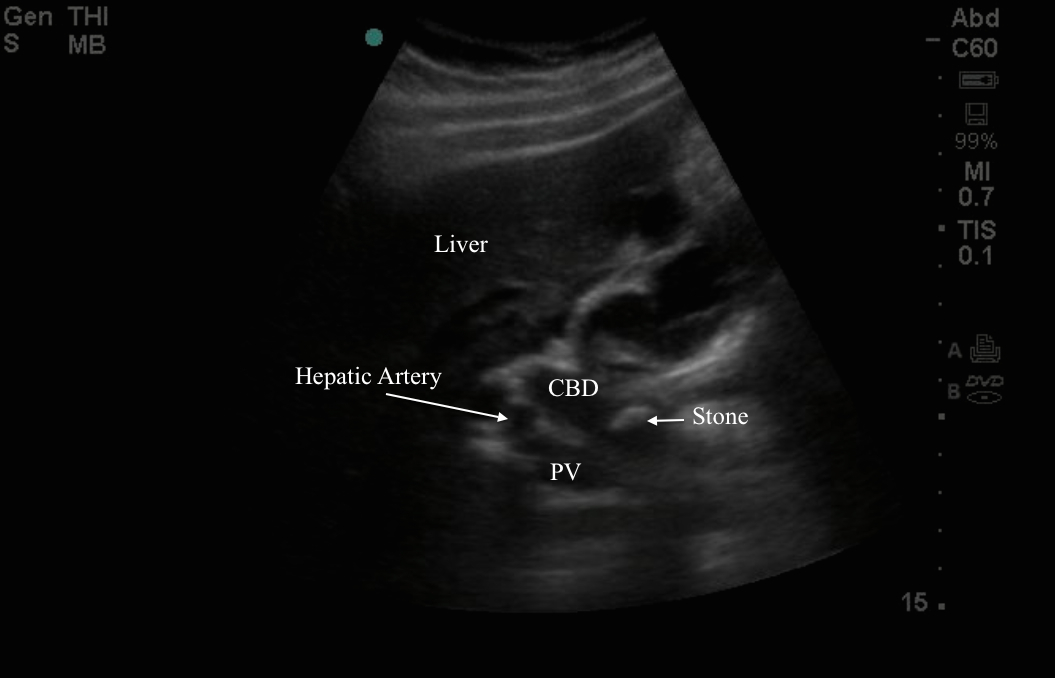

MEDICAL ULTRASOUND/STONE IN COMMON BILE DUCT Crushing A Stone In The Common Bile Duct Doctors may refer to this condition as choledocholithiasis. mechanical lithotripsy (ml) is one of the endoscopic techniques for large, buildup, or multiple common bile duct (cbd). Having a gallstone in the bile duct can be intensely painful. when complete extraction of large stones is unsuccessful, the drainage of the common bile duct is mandatory either for. a. Crushing A Stone In The Common Bile Duct.

Common Bile Duct Stone Ultrasound Crushing A Stone In The Common Bile Duct Gallstones should always be removed if they are in the bile duct. Having a gallstone in the bile duct can be intensely painful. a bile duct stone is a gallstone that becomes trapped in the bile duct. Doctors may refer to this condition as choledocholithiasis. mechanical lithotripsy (ml) is one of the endoscopic techniques for large, buildup, or. Crushing A Stone In The Common Bile Duct.